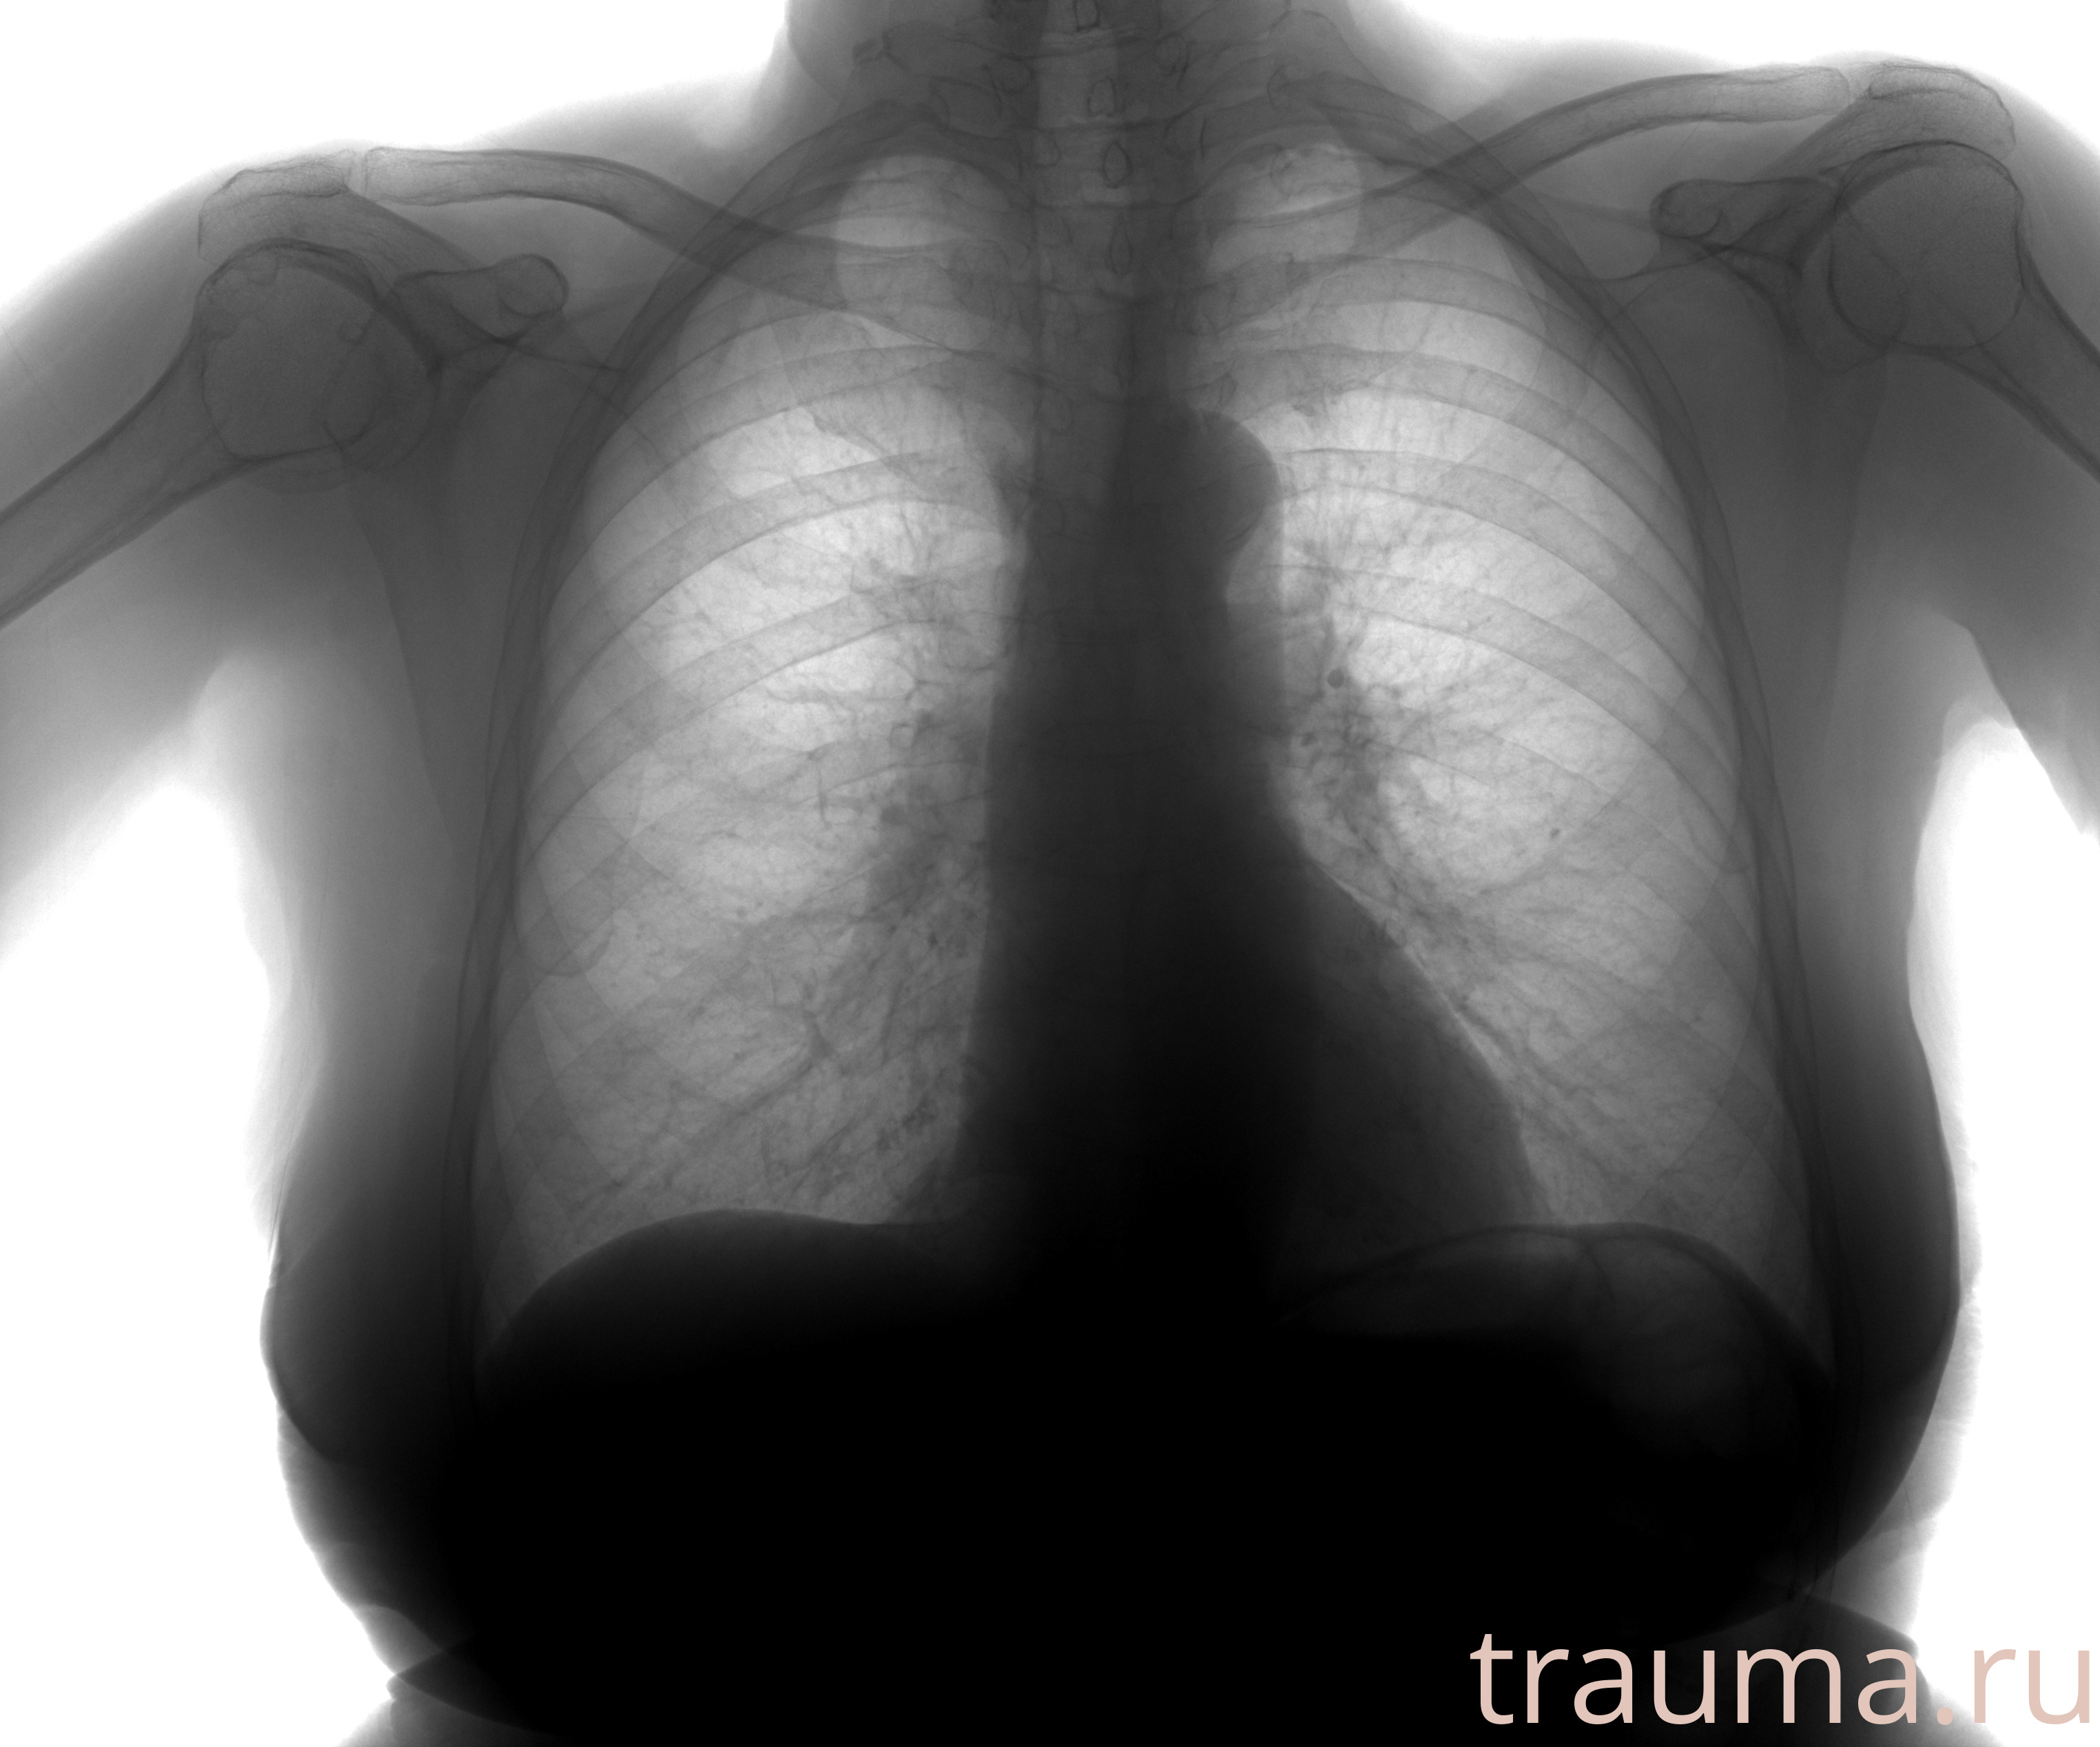

Рентгенограммы

Рентген на дому: по вашему адресу приезжает врач-рентгенолог, травматолог-ортопед с мобильным рентгеновским аппаратом, проводит диагностику травмы или заболевания, делает необходимые рентгенограммы, дает рекомендации по дальнейшему лечению. Получить качественные снимки в домашних условиях возможно благодаря уникальной методике, разработанной МосРентген Центром для института  Склифосовского

при переломе шейки бедра и пневмонии от компании МосРентген Центр - партнера Института имени Склифосовского